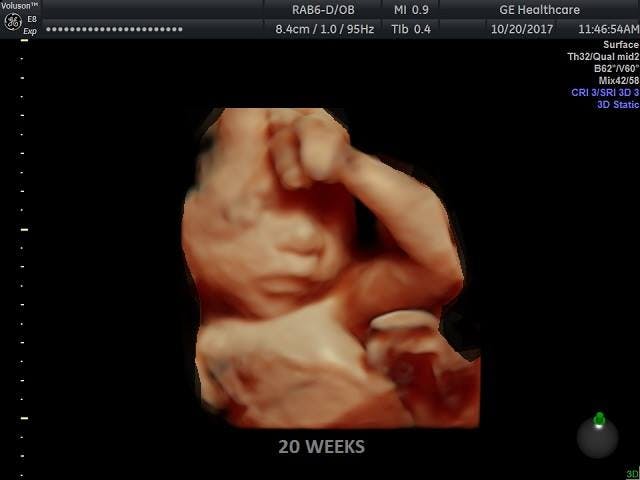

Famous Nilsson photo of a preborn baby at 20 weeks